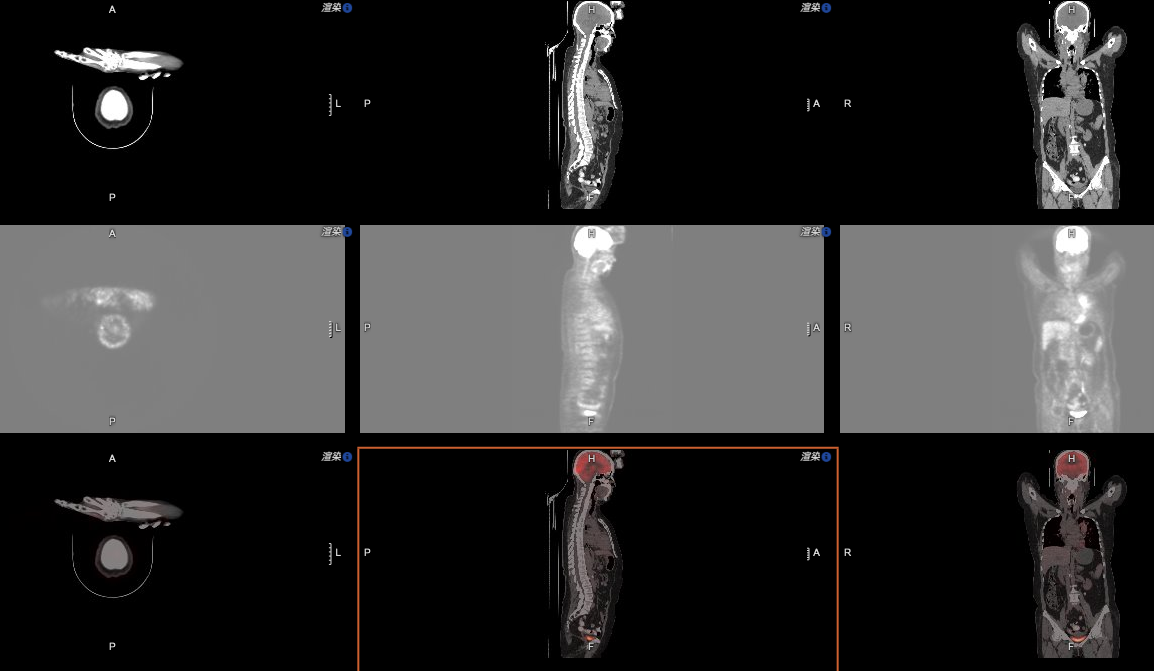

幾乎所有PACS軟件都具備縮放、平移、調窗、測量、電影功能,這部分功能適用于平片、DSA等;也具備分窗、MPR、MIP、VR功能,適用于CT、MR。因此PACS工作站適用于絕大部分影像的后處理,是閱片寫報告的基本要求。那么,這些功能在移動端,采用B/S方式使用時,是不是仍然具備?是不是還適用于絕大部分類型的影像?如果是,那么可以認為具備閱片寫報告的功能要求;如果不是,顯然,對于部分類型的影像,閱片寫報告則相對困難,甚至可能無法判斷。看下這兩張圖:

再(zai)看這張(zhang)圖(tu):

圖片6.png

相信對于具(ju)備PET/CT的醫療(liao)機構來說(shuo),這(zhe)樣的影像軟件功(gong)能(neng)同樣是必需的。